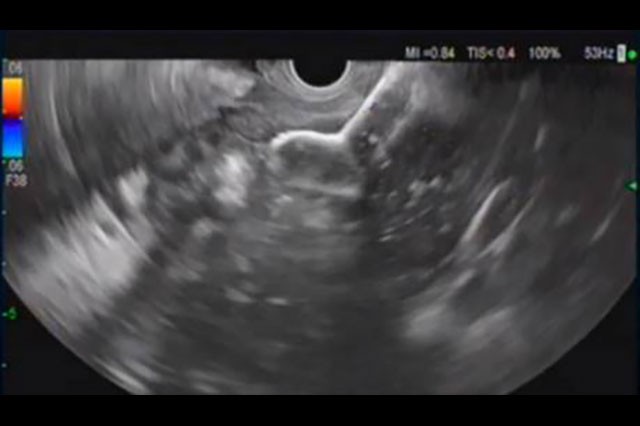

A Clinical Discussion of the 20mm AXIOS™ Stent

Physicians with experience placing the 20mm AXIOS™ Stent discuss in what clinical situations they chose to opt for the larger stent and if there were any benefits associated with the use of the larger diameter.